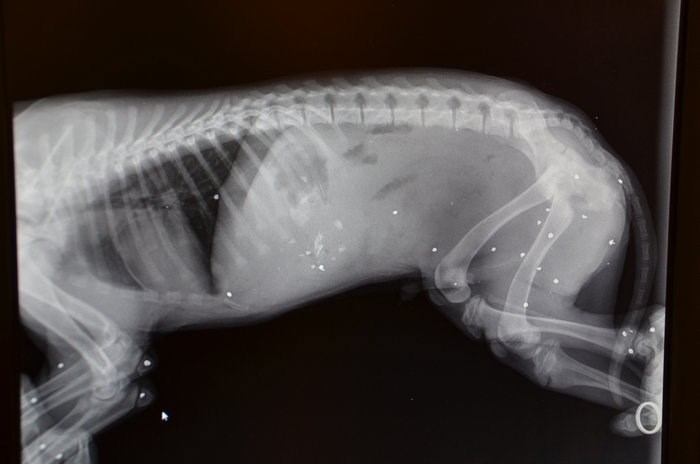

Ένα φρικιαστικό περιστατικό επίθεσης σε αδέσποτο ζώο σημειώθηκε στο Άργος, όταν ένας ασυνείδητος πολίτης πυροβόλησε ένα κουταβάκι μόλις τριών μηνών.Σύμφωνα με την καταγγελία του Φιλοζωικού Συλλόγου Άργους Λάιζα «βρίσκεται ήδη σε εξέλιξη η αυτόφωρη διαδικασία για τον συγκεκριμένο υπάνθρωπο που βγήκε και πυροβόλησε ένα κουτάβι τριών μηνών με εννιάρια φυσίγγια. Όπως επιβάλει ο νόμος, θα οριστεί δικάσιμος και θα οδηγηθεί στη δικαιοσύνη από την μάρτυρα που τον κατήγγειλε και από την αυτεπάγγελτη μήνυση της αστυνομίας».Αμέσως ενημερώθηκε ο Σύλλογος και έσπευσε στο σημείο μαζί με την Ασφάλεια Άργους, όπου και μετέφεραν το μικρό κουτάβι στον κτηνίατρο.Έπειτα από ακτινογραφίες, διαπιστώθηκαν πάνω από 25 θραύσματα μέσα στο κορμάκι του.